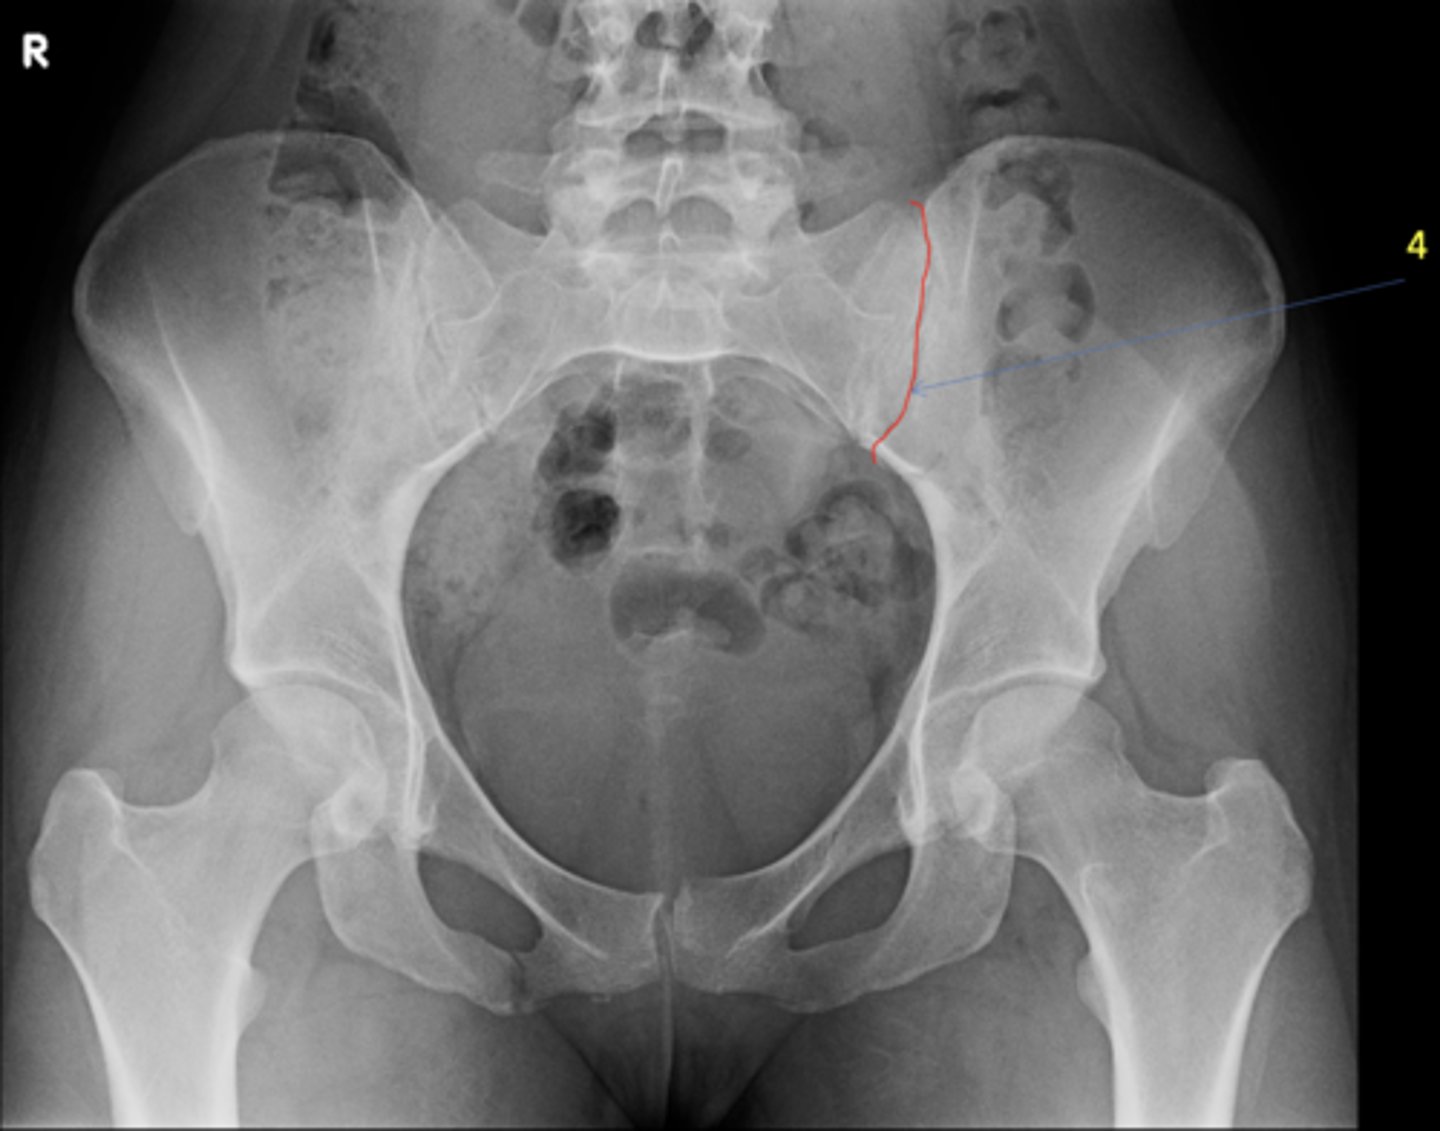

4

Risser's Classification Stage _____: apophysis over >75% of the iliac crest

<p>Risser's Classification Stage _____: apophysis over &gt;75% of the iliac crest</p>